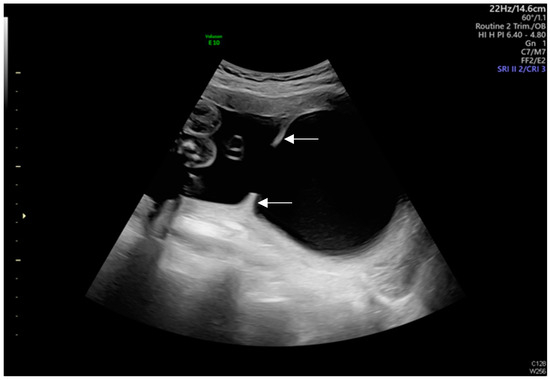

Intrauterine Adhesion-Induced Septated Amniotic Cavity: Ultrasonographic Findings in Second and Third Trimesters

Huang, J.-T.; Chen, Y.-M.; Tsai, C.-C.; Cheng, H.-H.; Lai, Y.-J.; Lee, P.-F.; Hsu, T.-Y.; Huang, K.-L. Intrauterine Adhesion-Induced Septated Amniotic Cavity: Ultrasonographic Findings in Second and Third Trimesters. Diagnostics 2024, 14, 2826. https://doi.org/10.3390/diagnostics14242826